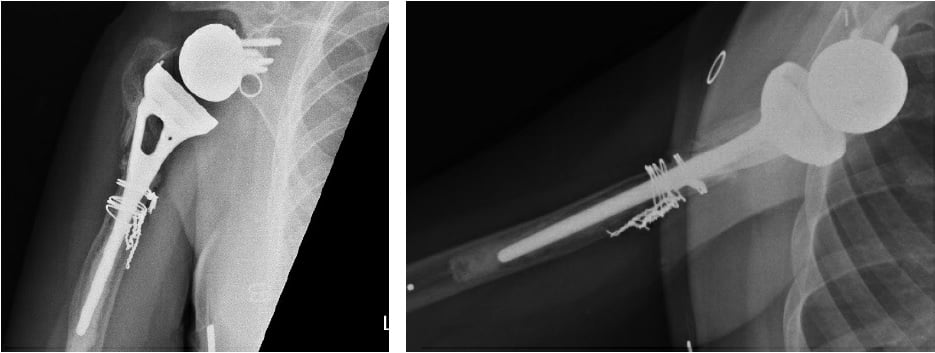

A 38-year-old woman presented to HSS in 2019 with a poorly functioning reverse total shoulder arthroplasty (rTSA) and pain at rest and with activity. After a malunion following a proximal humerus fracture in 2003, she had undergone several surgical procedures, including a valgus-producing osteotomy of the proximal humerus, removal of hardware, anatomic total shoulder arthroplasty (TSA) with an all-polyethylene glenoid, and finally rTSA with a cemented humeral stem in 2016 (Fig. 1). Symptomatic management had failed in the 3 years prior.

Figure 1: Initial X-rays show rTSA with a well-positioned glenosphere component and proximal humeral bone loss with radiolucency surrounding the humeral stem cement mantle.